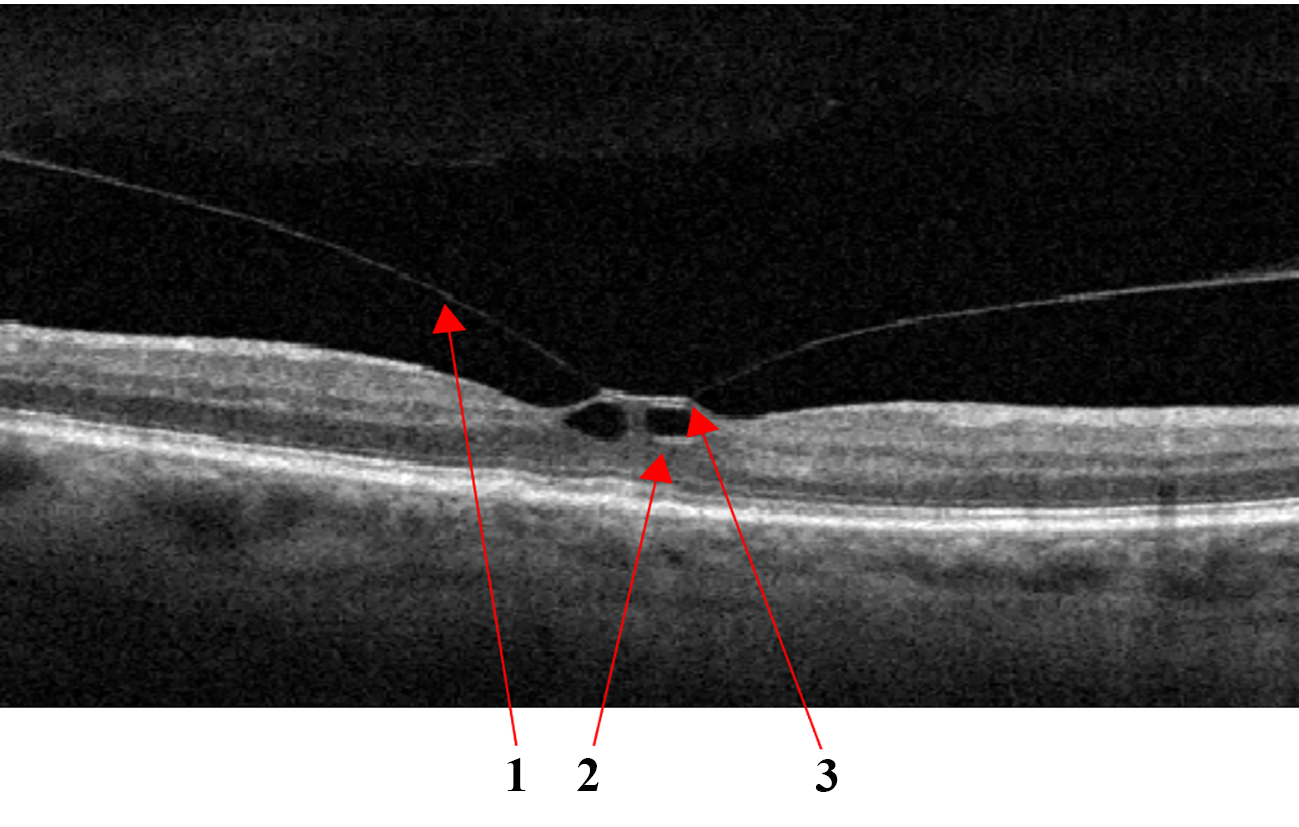

Epiretinal Membrane

ERM can develop idiopathically, secondary to intraocular surgery or inflammation, and are characterized by the proliferation of glial tissue on the retina’s inner surface in the macular area, Fig.7a. The Pathologic connective tissue overgrowth results in epiretinal fibrosis (fibrosis of the inner border membrane, epiretinal membrane). Clinically, the disease is characterized by thickening and wrinkling of the inner limiting membrane, sometimes called cellophane retinopathy, because of its appearance on fundus examination[40].

Refer to caption

((a))

((b))

Figure 7: VID by the epiretinal membrane (a); ERM with foveola deformity and Ectopia (b): 1 - ERM, 2 - Ectopia.

In epiretinal membrane maturation, the vireo-retinal traction can deform the retina, reducing visual acuity, cause metamorphopsia, and can lead to macular tears and holes. In such cases, there is an irreversible loss of visual function without timely surgical intervention requiring an epiretinal membrane peel[41].